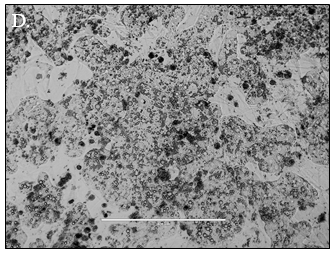

Predicting human hepatic clearance (CLhepatic) is often challenging in early drug development, particularly when low-clearance compounds are involved. To assess the metabolic stability of such drugs, suspended primary human hepatocytes (PHH) are commonly used; however, their ability to accurately predict in vivo CL, particularly of slowly cleared drugs, can be limited by short incubation times and rapid loss of enzymatic activity. To mitigate these issues, long-term in vitro models, like the Triculture System (TCS) developed by LifeNet Health, have been implemented in an effort to improve the characterization of hepatic metabolism and clearance in vitro by lengthening the amount of time hepatocytes can be cultured successfully. The TCS is an all-human cell-based in vitro model comprised of PHH and two different types of primary feeder cells (FC) that are plated together, shown in (Figure 1), on either a 24-well or 96-well collagen-I coated plate. In this study, the TCS (in both 24- and 96-well formats) was assessed for its functionality and its ability to predict human CLhepatic over the course of a 7- day incubation with no media change.

Hepatocytes in both the 24-well and 96-well formats appeared healthy morphologically and functionally demonstrated high levels of albumin secretion and relatively low levels of LDH release with no media change for up to 7 days when compared to values observed with daily media changes.